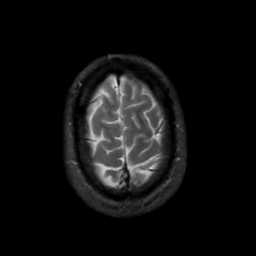

MR Study #2, February 17, 1991 -- Slice #44

[Home][Help][Clinical][Tour 1][Tour 2] Slice 44